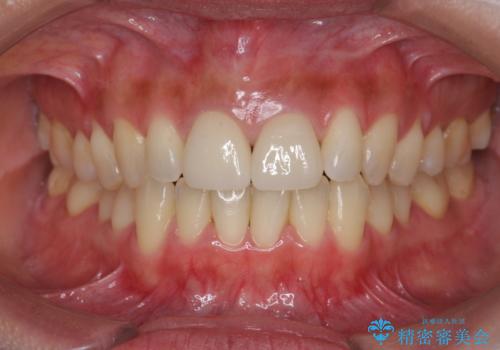

- 3週間後に迫った結婚式までになんとか前歯をきれいにしたいという希望で来院されました。

一回の治療時間を長く取り、限られた時間で最大限の結果を出せるよう集中治療を計画します。

ただ見えるクラウンを白くきれいにするのではなく、長期的な歯の予後を考えると根管治療・ファイバーコア築盛・精密な歯牙形成等クリアすべき条件は多々あると言えます。